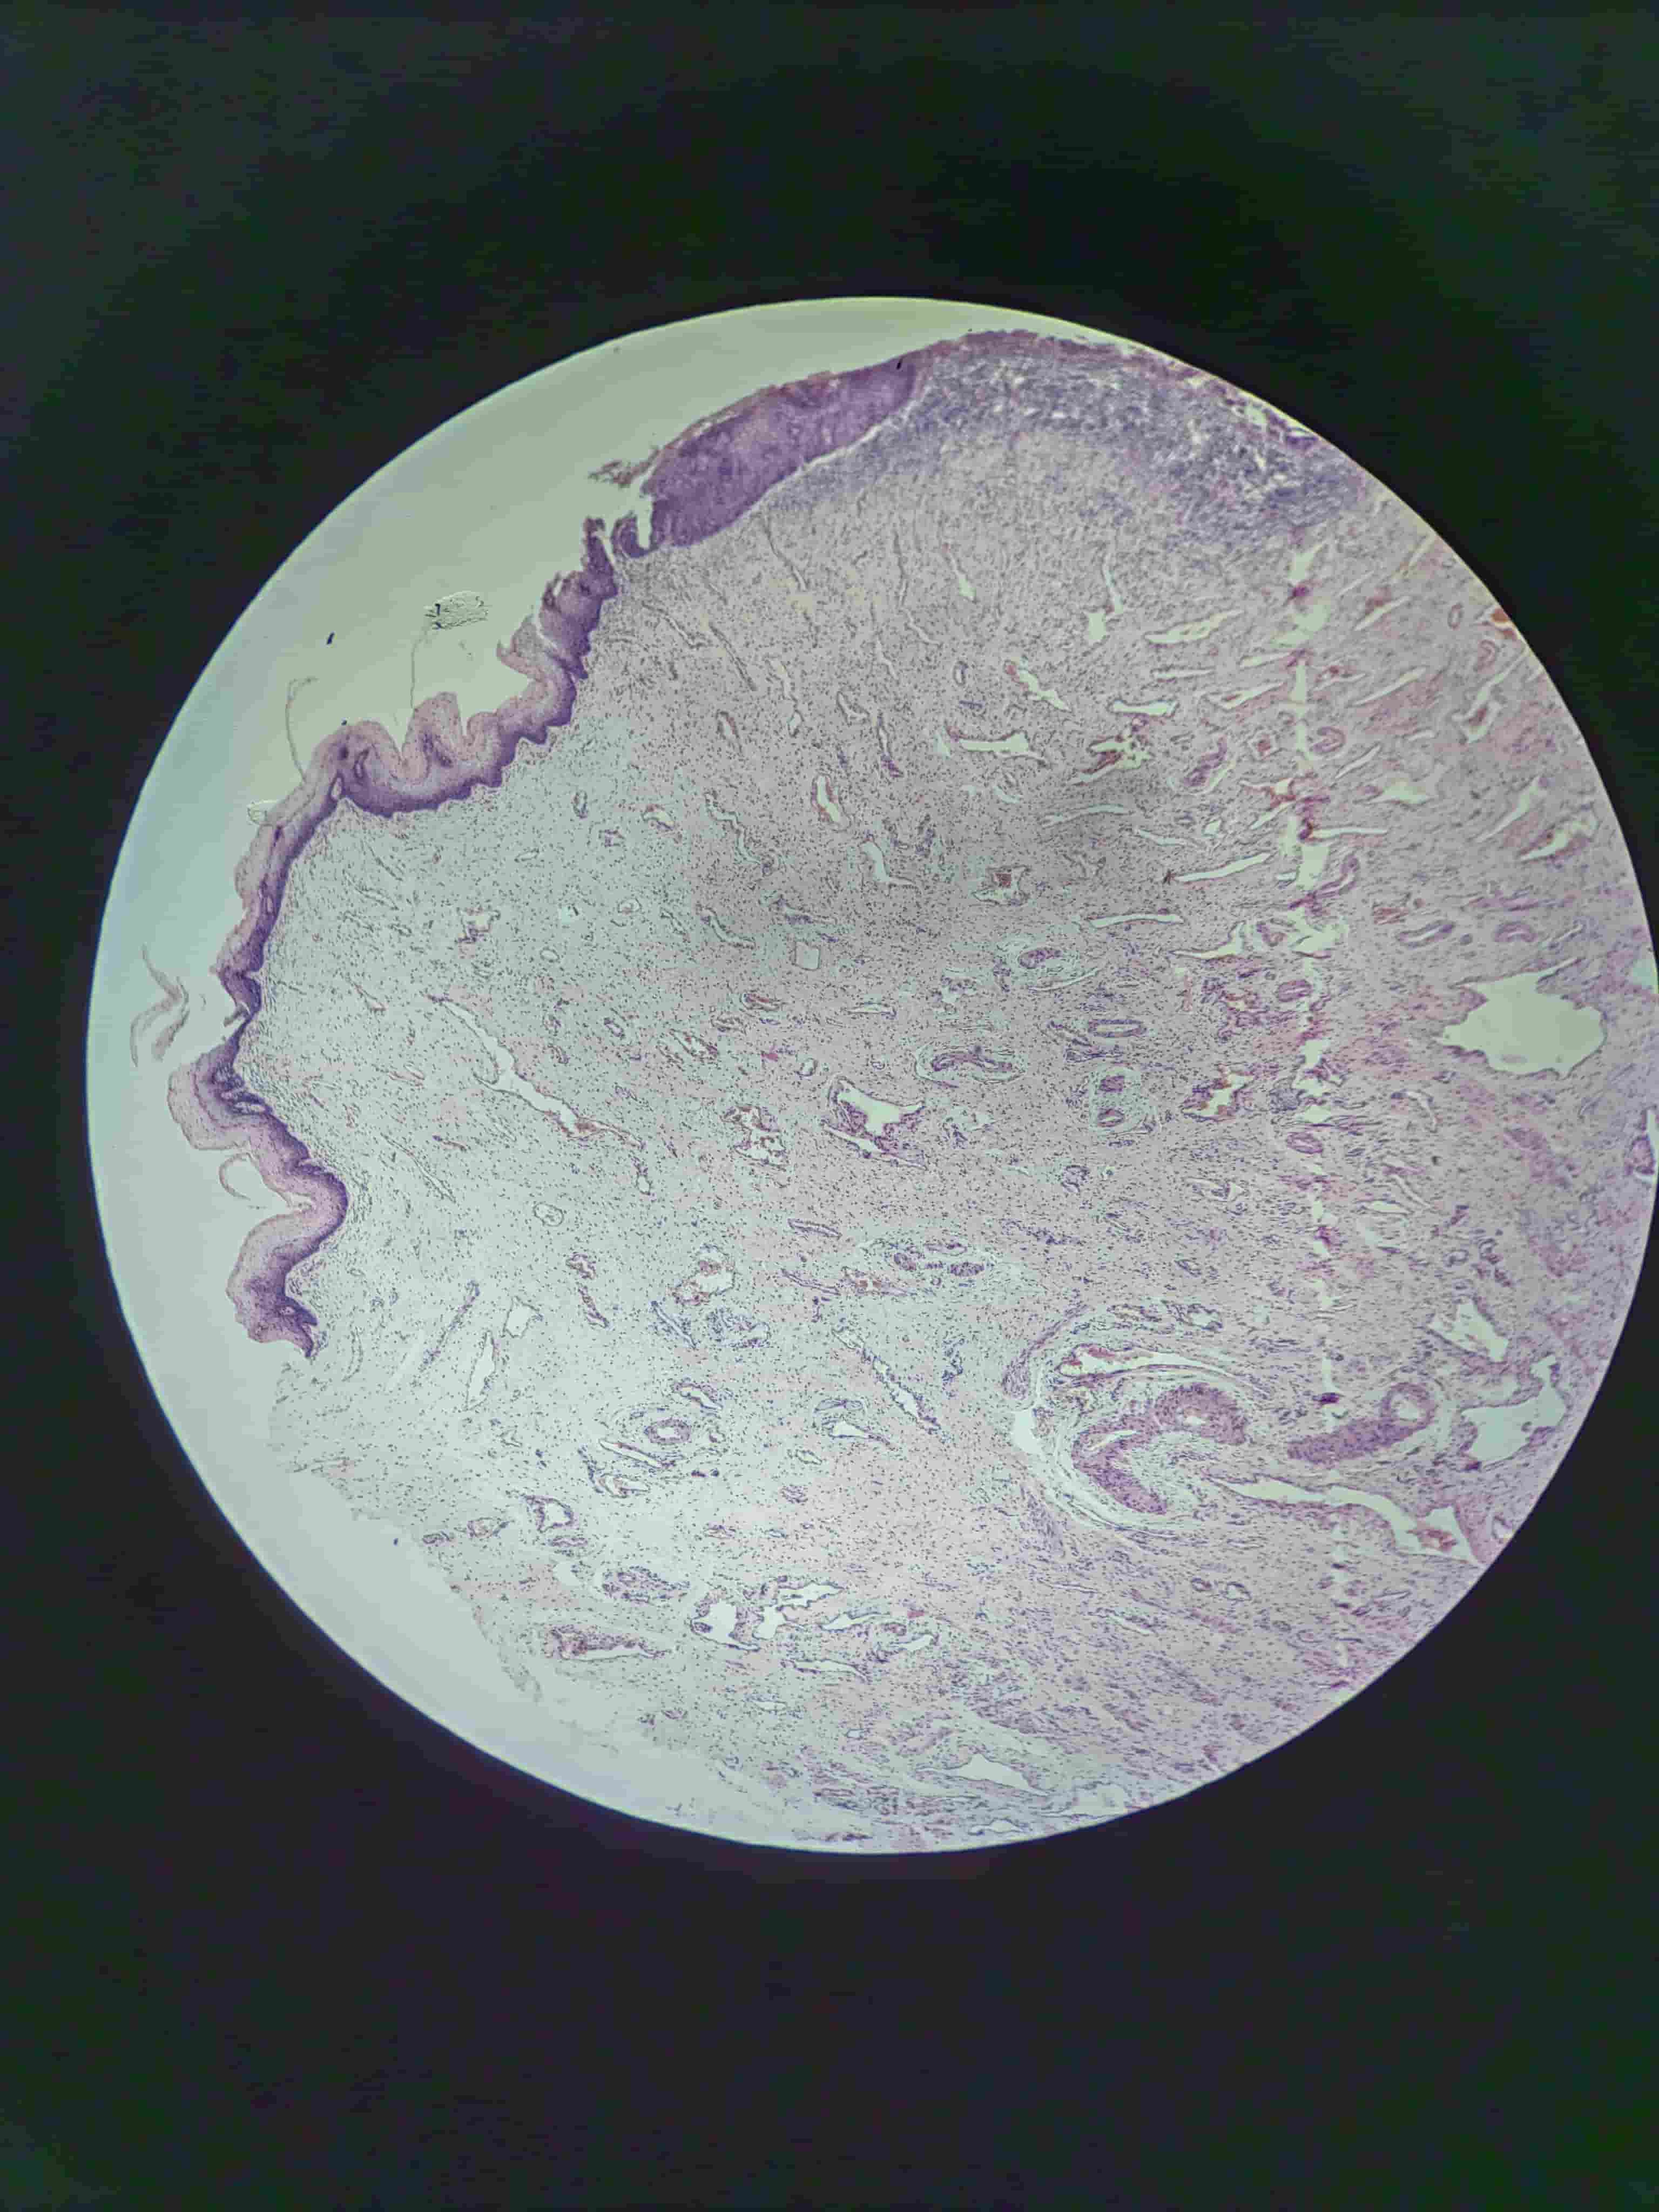

皮肤乳头状瘤